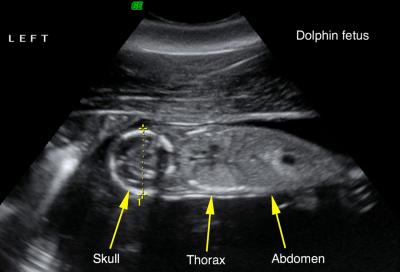

In August of 2011, a team of independent and NOAA scientists evaluating the health of bottlenose dolphins in Louisiana's Barataria Bay gave dolphin Y35 a good health outlook. Based on the ultrasound, she was in the early stages of pregnancy, but unlike many of the other dolphins examined that summer day, Y35 was in pretty good shape. She wasn't extremely underweight or suffering from moderate-to-severe lung disease, conditions connected to exposure to Deepwater Horizon oil in the heavily impacted Barataria Bay.

Among the pregnant dolphins being monitored in this study, at least two lost their calves before giving birth. Veterinarians confirmed with ultrasound that one of these dolphins, Y31, was carrying a dead calf in utero during her 2011 exam. Another pregnant dolphin, Y01, did not successfully give birth in 2012, and was then seen pushing a dead newborn calf in 2013. Given that dolphins have a gestation of over 12 months, this means Y01 had two failed pregnancies in a row.